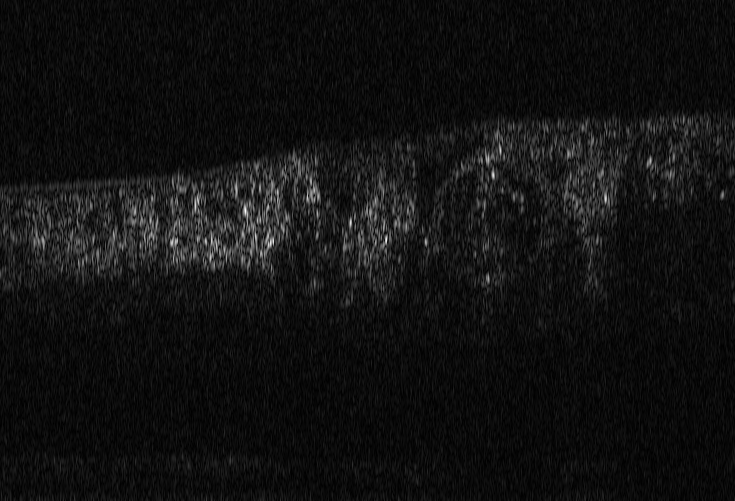

Refer to caption

(a) Reference

(b) (22.8, 0.97, 0.08)

(c) (21.2, 0.96, 0.07)

Figure 8: Chest X-Ray scans with different kinds of post-processing; (a) serves as reference, (b) is wrongly judged as better visualization by PSNR and SSIM, LPIPS gives a slightly worse evaluation for (b).

In Figure 7, contrast deviation and edge enhancement were reduced in (b), but increased in (c), the noise reduction algorithm was removed in both. The brightness was increased in both images but more so in (c) and low-contrast enhancement was removed in (b). The result is that (b) has relatively low contrast in the lungs compared to the reference (a) and radiograph (c). In Figure 8, edge enhancement has been dramatically increased in (b), whilst the contrast deviation and tissue contrast have been reduced. In (c), the brightness, tissue contrast and edge enhancement have been slightly increased. Consequently, (b) provides low contrast in the lungs with excessively prominent lung markings and vasculature which make it harder to detect abnormalities such as a pneumonia.

FR-IQA mismatches

In Figure 7 and 8 we apply the standard FR-IQA metrics to the images with diverging quality. Although it is visually obvious that image (b) has lower visual quality, it is judged wrongly as the better image by all measures in the first example Figure 7, and the results in (b) and (c) of the second example Figure 8 are quite close, where PSNR and SSIM are also providing the wrong order. This indicates that the tested standard FR metrics are not suitable to evaluate the quality of data sets with X-Ray images that have large variations regarding contrast, luminance and sharpness.